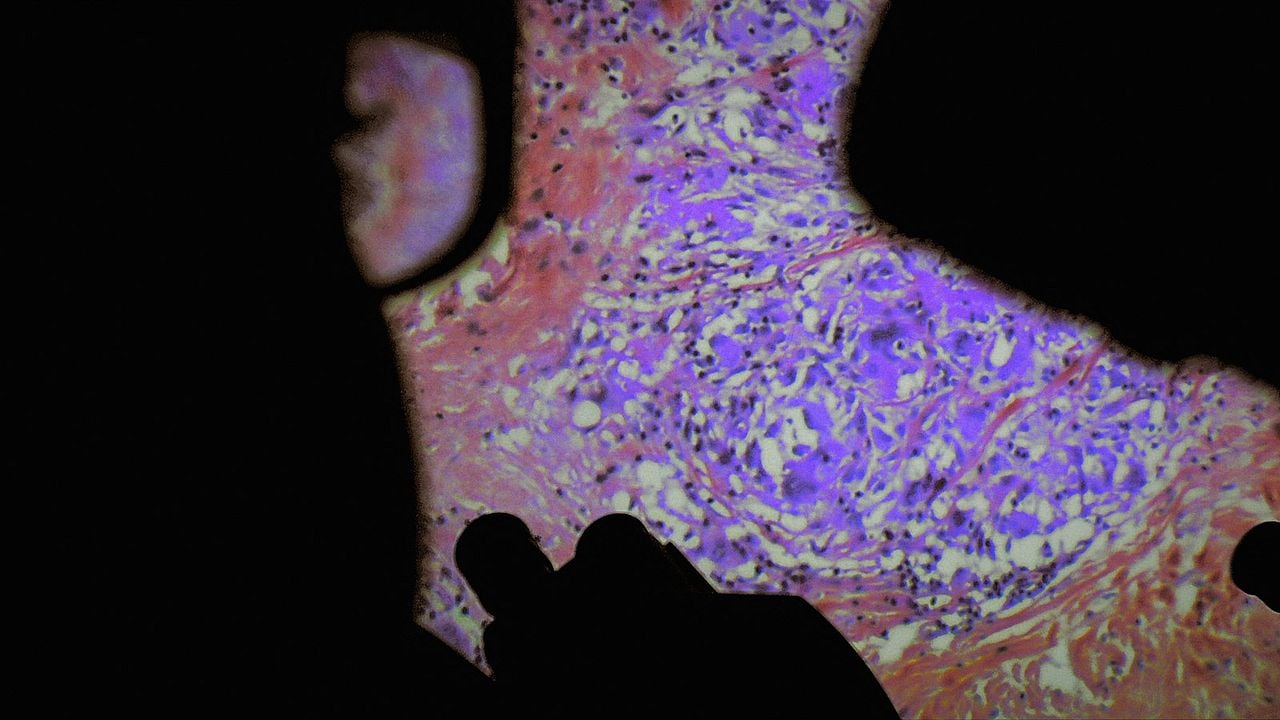

De Humani Corporis Fabrica : Bild

Bild hinzugefügt am 5. Mai 2022

Copyright Les Films du Losange

De Humani Corporis Fabrica